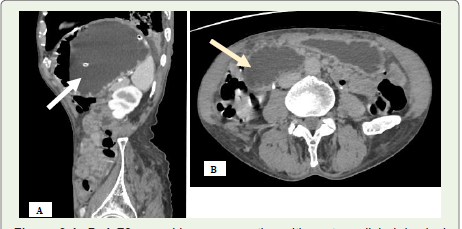

during CT imaging for unrelated issues [1,7,8] [Figure 2].CT imaging findings:

Multidetector CT (MDCT), due to its high spatial resolution,

enables clear visualization of the median arcuate ligament—thickness

beyond 4 mm is considered abnormal [8] [Figure 1B]. Since axial

images may not reveal the full extent of compression, sagittal

reconstructions are essential to assess both the ligament and celiac

artery origin. A distinctive hooked or “J-shaped” narrowing at the

origin of the celiac artery (Figure1A) serves as a key imaging sign

distinguishing MALS from atherosclerotic changes. The compression

is often persistent, even during inspiration. Additional findings may

include post-stenotic dilatation and development of collateral vessels

such as the pancreaticoduodenal arcade from the superior mesenteric

artery [9].Management:

Figure 1A and B:A 49-year-old man presenting with abdominal pain after

meals. (A) Sagittal contrast-enhanced CT angiogram of the abdomen

reveals a prominent median arcuate ligament (black arrow), causing a

hooked deformity and narrowing at the proximal celiac artery with poststenotic

dilatation. (B) Axial contrast-enhanced CT angiogram demonstrates

the celiac artery origin being compressed by the thickened median arcuate

ligament (black arrow).

Figure 2:A 77-year-old man evaluated for haematuria and diagnosed with

bladder carcinoma (white arrow). Incidentally noted on sagittal contrast enhanced

CT angiography is a kinked proximal celiac artery with a hooked

contour and associated post-stenotic dilatation.